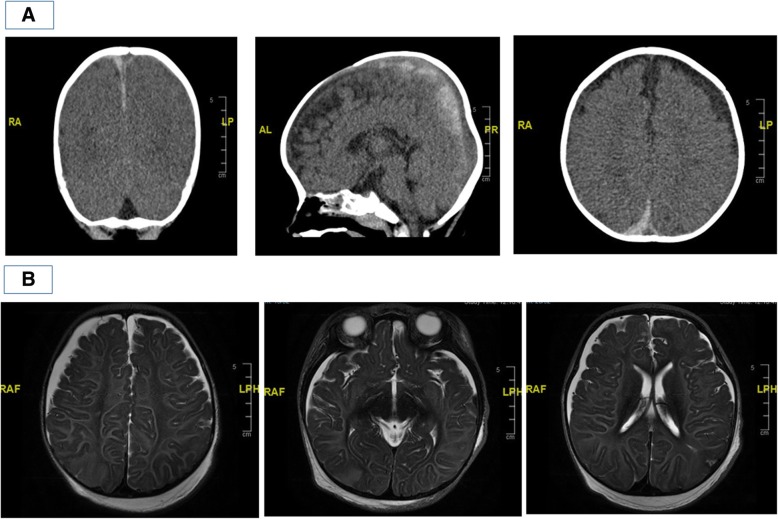

Fig. 1.

a CT brain done at Children’s Emergency showing bilateral subdural haemorrhages. b MRI brain done two days off ECMO (T2-weighted images) showing patchy areas of cortical swelling and reduced grey-white differentiation in the respective lobes; leftmost image: right parietal lobe; middle image: occipital lobes; rightmost image: left parietal lobe

At our Children’s Emergency, about 45 min after initial resuscitation, his vital signs were reflective of ongoing sympathetic overdrive. He was severely tachycardic (heart rate was 180 beats/minute) and markedly hypertensive despite repeated non-invasive blood pressure measurements from all limbs (blood pressure was 191/120 mmHg). He also had frequent desaturations to SpO2 80 to 90% (on FiO2 100% via bag-and-mask ventilation) with audible leak. He was poorly perfused but central pulses were present. Bilateral diffuse crackles were heard on lung auscultation, and there was large amount of frothy endotracheal tube (ETT) secretions that required frequent tube suctioning. Dual heart sounds were appreciated with no murmur. Liver edge was felt 1 cm below right subcostal margin, and no organomegaly was noted. Neurological examination revealed generalised hypotonia, areflexia, with no plantar response elicited, likely due to residual muscle relaxant effect. There were no external injuries found. Fundoscopy was not possible as his pupils were pinpoint due to ongoing midazolam infusion. Further history from his childcare teacher and both parents did not suggest an apparent unifying diagnosis for his clinical presentation then. Computed topography (CT) scan of the brain showed acute subdural haemorrhages along the posterior falx, left tentorial leaflet and overlying both high parietofrontal convexities. No significant mass effect, hydrocephalus, brain herniation or acute territorial infarct was noted (Fig. 1a). As he continued to have frequent recurrent desaturations despite ETT suctioning which by then yielded blood-stained frothy secretions, he was re-intubated with Size 4.5 cuff ETT (previous ETT was Size 4, uncuff), as these events were attributed initially to high leak and resultant inadequate ventilation. Prior to transfer to the paediatric intensive care unit (PICU), his blood pressure had returned to normal values, but his SpO2 continued to fluctuate between 80 to 90% on FiO2 100% despite high ventilatory pressures. Neuroprotective measures were instituted.

This was a dangerously ill 9-month-old boy who was previously well presenting with several clinical problems – firstly, convulsive status epilepticus as a result of acute severe brain injury for which CT imaging revealed bilateral acute subdural haemorrhages despite not having a known history of trauma; secondly, rapidly deteriorating cardiogenic shock with resultant flash pulmonary oedema resulting in respiratory failure despite being on high ventilatory support, finally requiring ECMO support. Possible differential diagnoses considered for his acute brain injury were that of underlying undiagnosed bleeding diathesis, intracranial vascular malformation, aneurysm or neoplasia, cerebral infections, rare metabolic disorders such as glutaric aciduria, and lastly non-accidental injury (NAI). His initial coagulation profile and full blood count were both normal, and had no previous or family history suggestive of an underlying bleeding diathesis. His clinical presentation, initial white blood cell count and inflammatory markers did not suggest bacterial sepsis or meningitis, and later viral studies did not suggest viral encephalitis. Magnetic resonance imaging (MRI) brain that was done 2 days after decannulation from ECMO showed bilateral subdural haematomas and mild sulcal subarachnoid haemorrhage. There was diffuse symmetrical white and grey matter signal abnormality and focal areas of parenchymal swelling. These features were suggestive of diffuse brain injury, which may have been a result of hypoxic-ischaemic injury, post-seizure changes, toxic and metabolic derangements or post-trauma changes (Fig. 1b). Magnetic resonance angiography (MRA) brain scan and transcranial doppler (TCD) of major cerebral vessels were both normal. Comprehensive metabolic workup did not reveal any underlying metabolic disorder. Slit-lamp examination of the eyes, which was done on the second day of admission, revealed extensive acute bilateral intra-retinal haemorrhages (Fig. 2b), raising the possibility of shaken baby syndrome. A full skeletal survey did not reveal any other bone fractures. A thorough investigation by the local justice system did not uncover any proof of NAI at home or at his childcare centre.